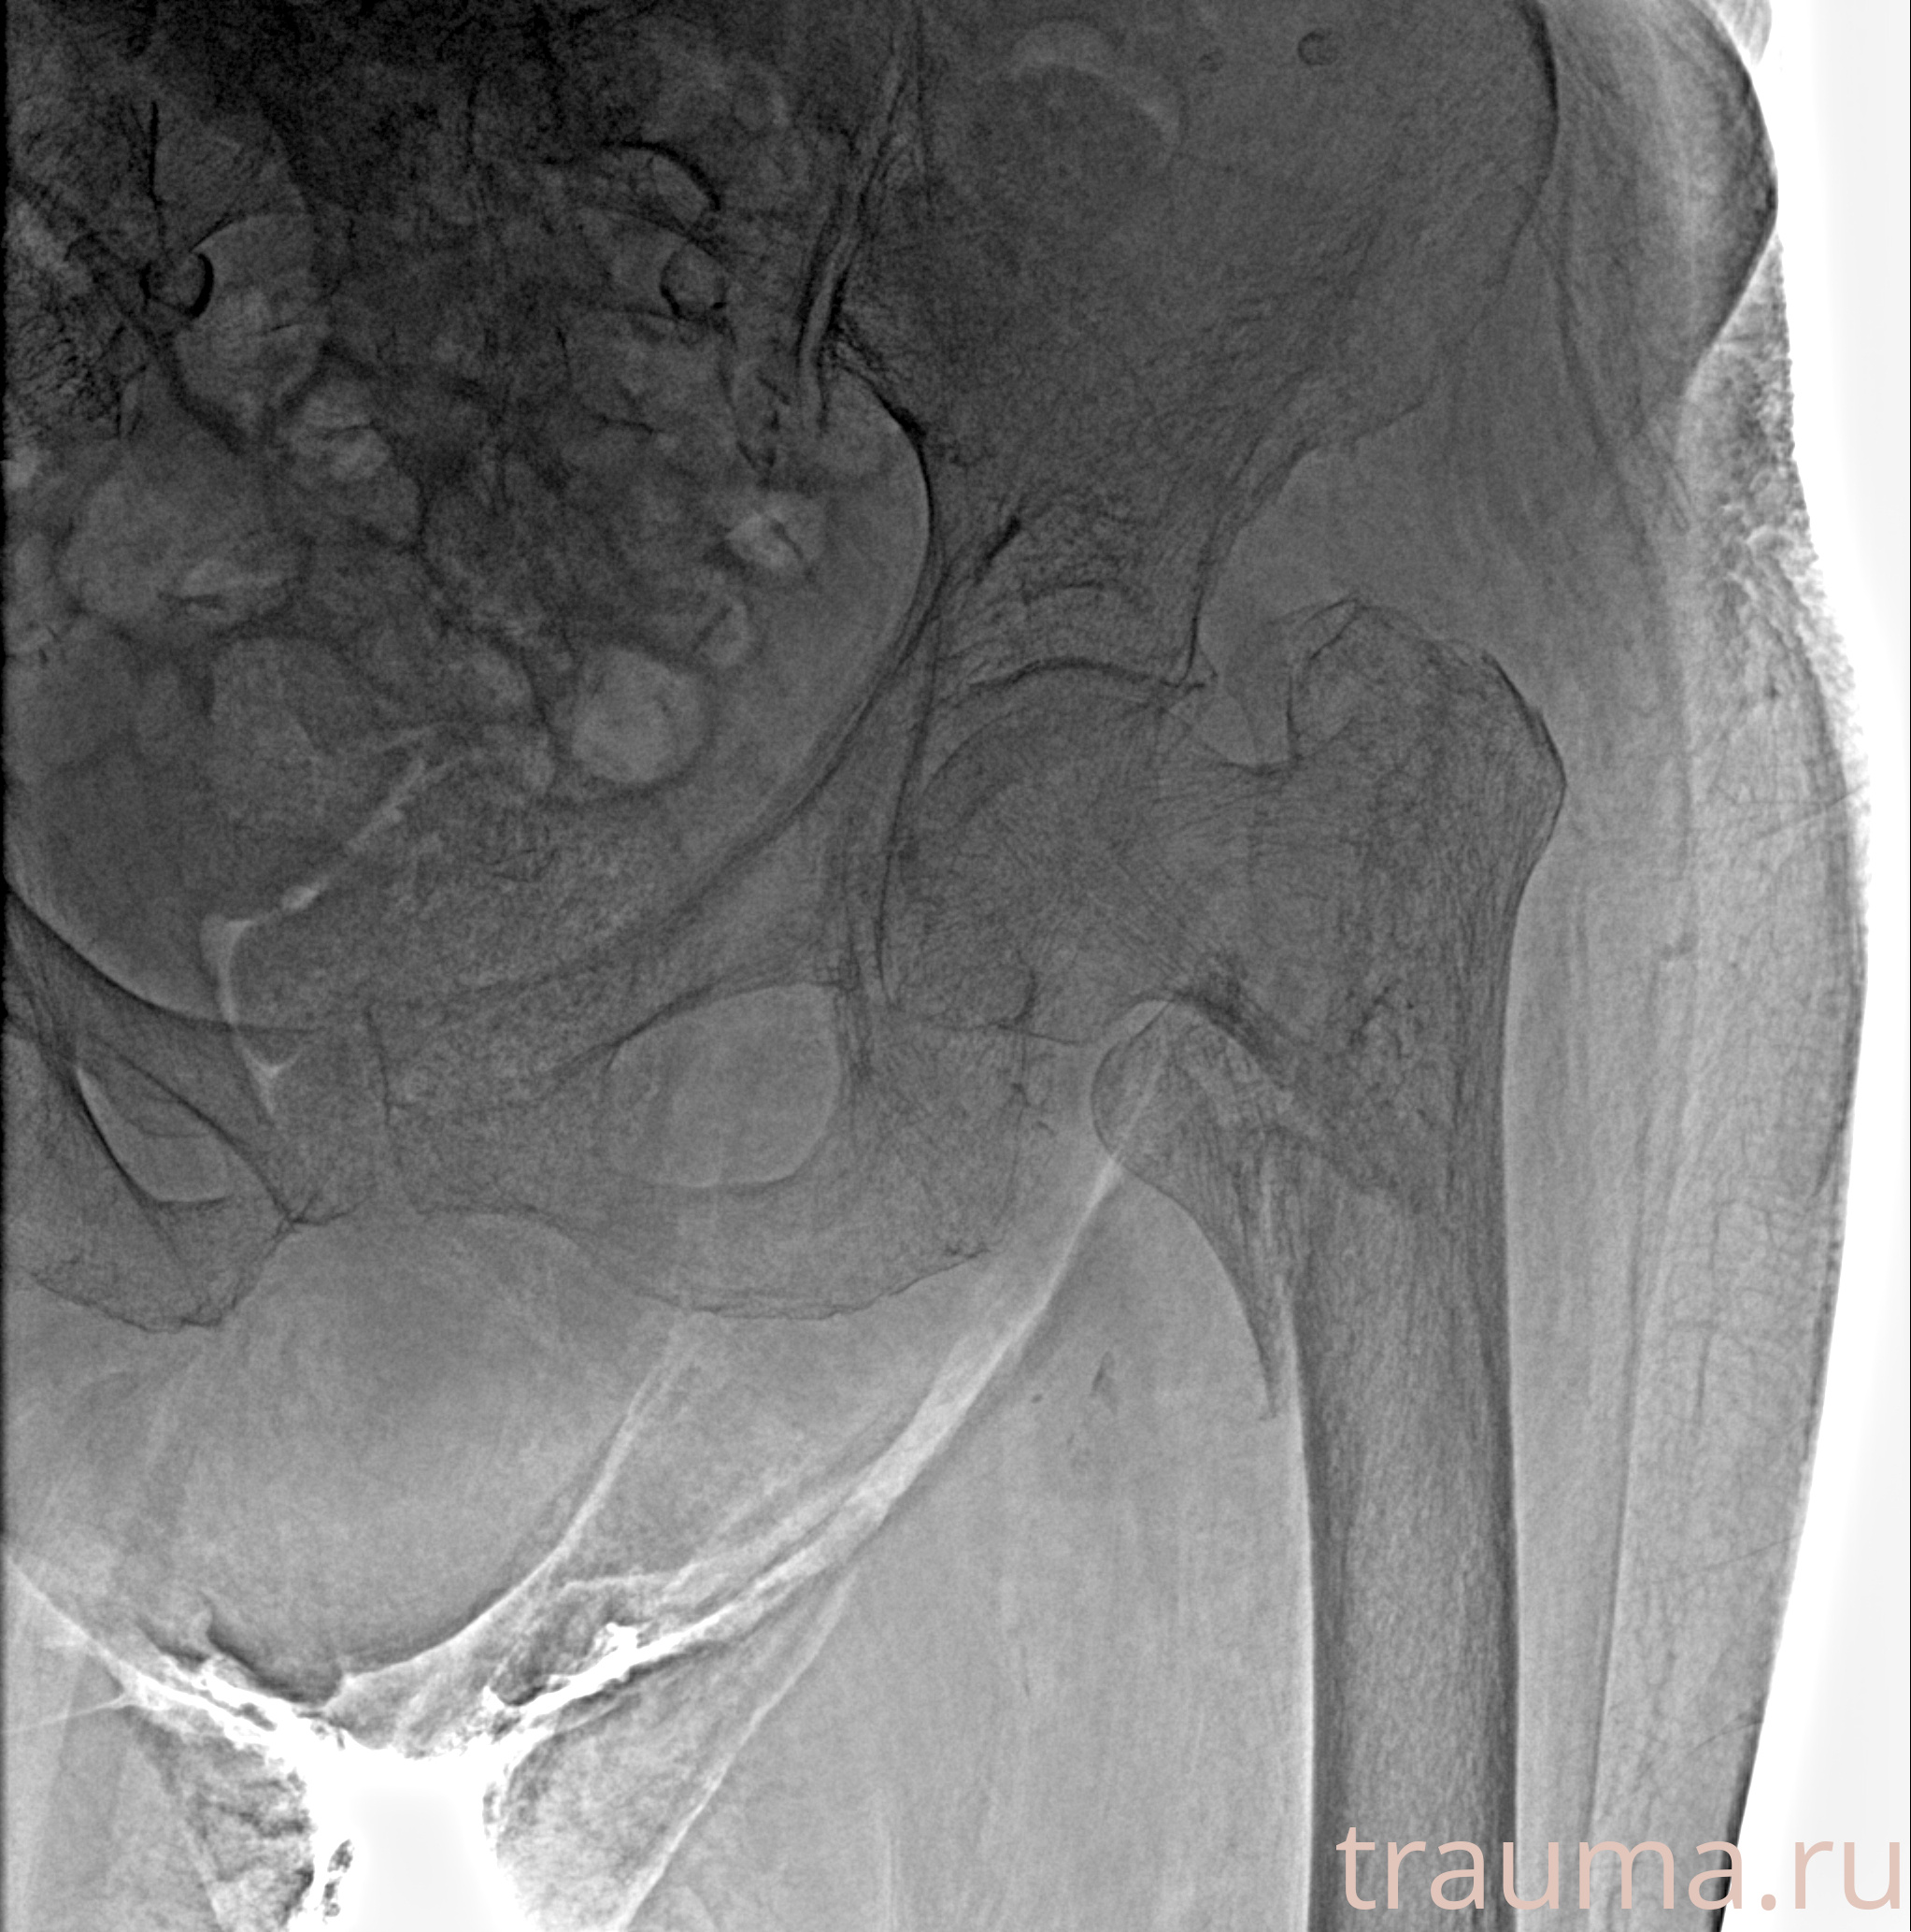

Рентген на дому: по вашему адресу приезжает врач-рентгенолог, травматолог-ортопед с мобильным рентгеновским аппаратом, проводит диагностику травмы или заболевания, делает необходимые рентгенограммы, дает рекомендации по дальнейшему лечению. Получить качественные снимки в домашних условиях возможно благодаря уникальной методике, разработанной МосРентген Центром для института  Склифосовского